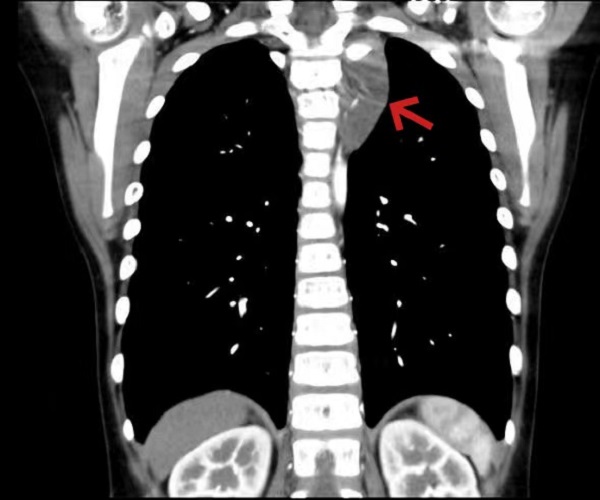

箭头所示为长入椎间孔之纵隔肿瘤

一一(化名)是一个8岁的男孩,从小开始一侧面部和对侧躯干就出汗少,家长未重视。2个月前左侧胸部出现针刺样疼痛,休息后疼痛会缓解。一周前因流行性感冒到儿童医院呼吸科门诊,胸部CT检查发现左侧纵膈内有一肿瘤,大小和鸡蛋差不多。呼吸科医生嘱托转心胸外科就诊收治入院后,经检查发现是神经来源肿瘤,明确了肿瘤位置在左侧后上纵膈胸椎旁。经过术前仔细的读片,发现肿瘤已经往椎间孔里生长,虽然还没有侵犯到脊髓,但是完整切除不仅难度大、而且容易损伤脊髓神经,也容易有肿瘤的残留导致术后复发。术前血液科会诊,完善相关检查均未能明确肿瘤病理性质,须手术治疗。